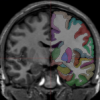

Manually Labeled MRI Brain Scan Database

This is a continuously growing and improving database of high-quality neuroanatomically labeled MRI brain scans, created not by an algorithm, but by neuroanatomical experts. All results are checked and corrected. Regions of interest include the usual sub-cortical structures (thalamus, caudate, putamen, hippocampus, etc), along with ventricles, brain stem, cerebellum, and gray and white matter. We also sub-divide the cortex into "parcellation units" that are defined by gyral and sulcal landmarks. There are 157 ROIs now and more to come.